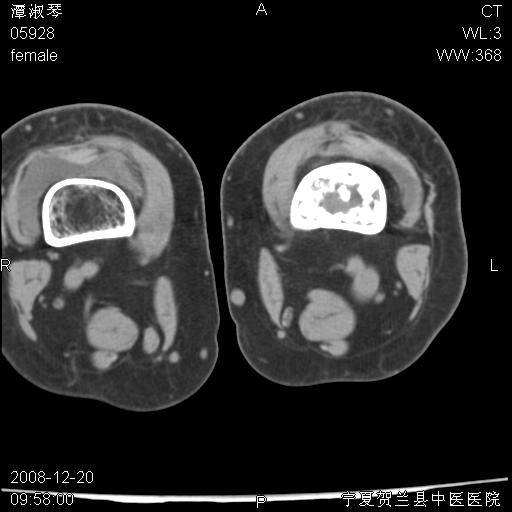

标题: CT17526:请各位看看是啥?

支持骨梗死,退行性骨关节病,膝关节积液.

考虑骨梗死可能性大

骨梗死可能性大

左股骨下段骨梗死。双膝退变。

左胫骨下端松质骨及髓腔内可见点片状高密度灶,骨皮质无明显膨胀及变薄。病变范围较长。支持骨梗死,退行性骨关节病,膝关节积液